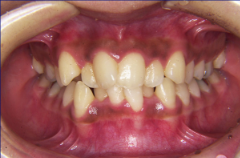

装置装着前